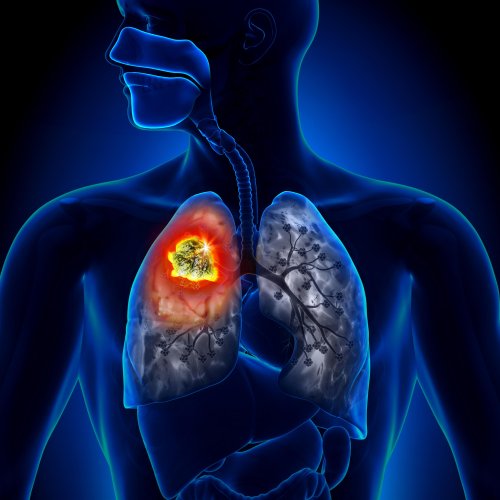

Инфаркт легкого – это кислородное голодание участка легочной ткани, которое наблюдается из-за того, что кровь, несущая кислород, не поступает к тканям. Препятствие току крови в свою очередь происходит из-за возникновения барьера в кровеносном сосуде, кровоснабжающем определенный участок легочной паренхимы.

Чаще всего кислородное голодание легкого наступает из-за тромбоза (образования кровяного сгустка на внутренней стенке артерии, закупоривающего ее просвет) или эмболии (закупорки инородным телом, принесенным с током крови из любого участка человеческого тела – в данном случае оно называется эмболом). Реже патологический процесс наступает из-за сдавливания кровеносного сосуда извне. Инфаркт легкого также называют легочной эмболией, подразумевая под эмболией закупорку сосуда в общем, независимо от закупоривающего фактора.

В силу анатомических особенностей инфаркт легкого случается на ограниченном сегменте (участке) ткани легкого, так как тромбом или эмболом закупориваются отдельные артерии – долевые, сегментарные или более мелкие. Множественной эмболии могут подвергнуться сосуды мелкого калибра, но они кровоснабжают небольшой участок легкого – благодаря этому кислородное голодание органа не тотальное, а ограниченное.

В силу строения легкого его участок, пострадавший от нехватки кислорода, по форме похож на пирамиду (или клин). Ее верхушка направлена в сторону корня легкого, а основание – в противоположную сторону.